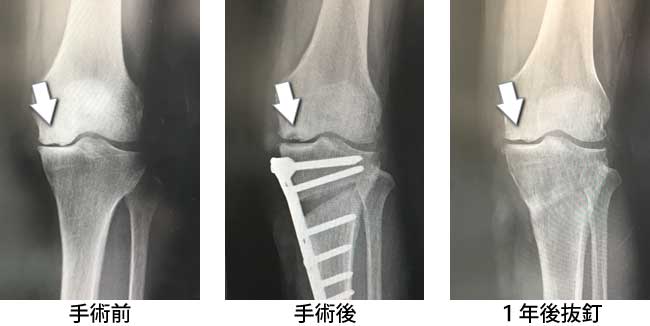

- ▼左変形性膝関節症、特発性大腿骨内顆壊死にて手術適応になった症例です。

(人工骨の充てん無し)

- 変形性膝関節症の初期~中期にかけての患者さまが対象となります。膝関節の近くで脛骨の一部を内側から切り、その部分を楔状に広げ、体重が外側にかかるよう矯正します。楔状に広げた部分には必要に応じて「人工骨」を充てんし、金属製のプレートで固定します。充てんした人工骨は時間が経つうちに骨と一体化していきます。骨が再生していることを確認されれば最終的に金属製プレートを抜去することができます。